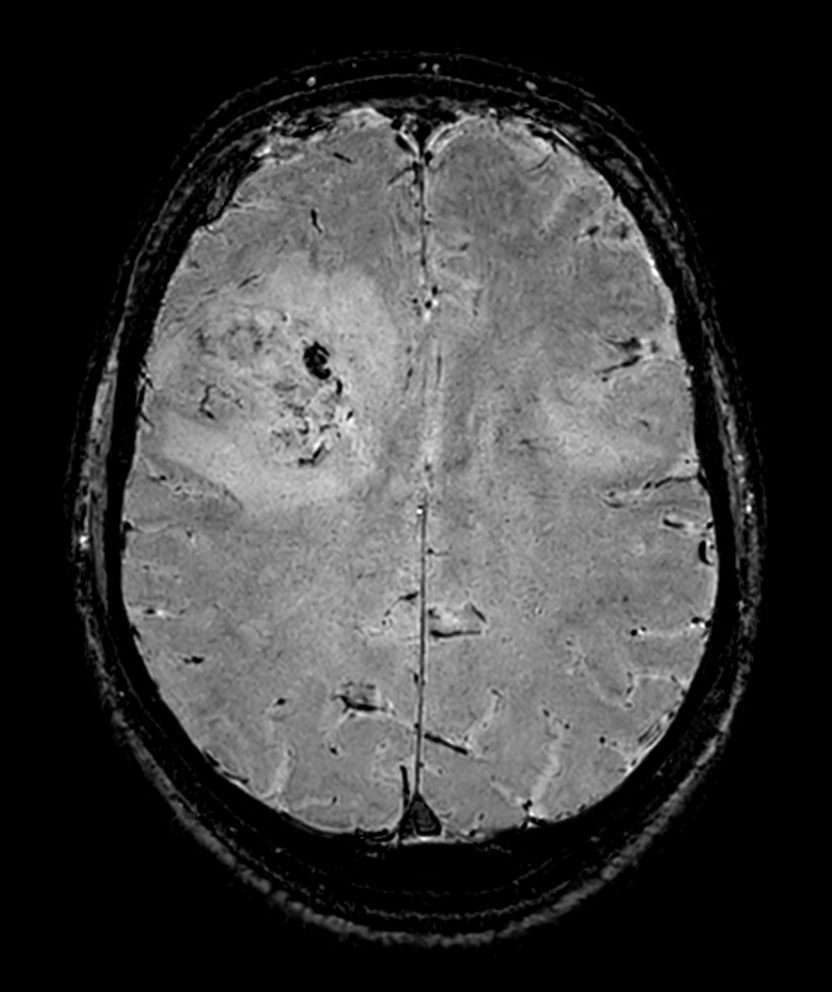

Axial 3D T1w TFE with gado